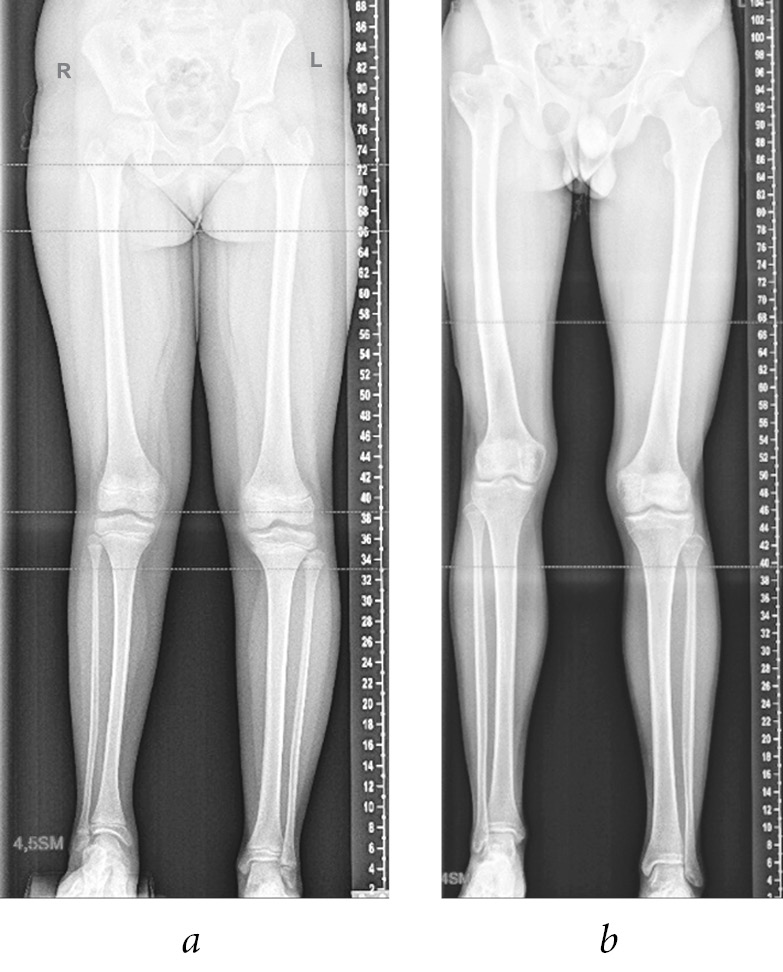

The patient records and results of radiation examination of the main groups of pediatric patients were analyzed. Group 1 was the control group, and group 2 included 11 pediatric patients aged 8 to 16 years (mean age, 11.9 ± 1.05 years) with congenital shortening of the lower extremity and hypofunction of metaepiphyseal epiphyseal cartilage of the femur and tibia. The degree of involvement in the pathological process of the epiphyseal zones of the affected extremities was not evaluated. The average difference in the length of the lower extremities was Δl = 4.8 ± 0.80 cm (Fig. 1, a). Group 3 included 11 patients aged 9 to 16 years (mean age, 12.2 ± 0.78 years) with acquired shortening of the lower extremity with destructive changes in the proximal metaepiphyseal femoral growth zone after acute hematogenous osteomyelitis. The average difference in the length of the lower extremities was Δl = 4.5 ± 0.38 cm due to the shortening of the femoral length (Fig. 1, b). Patients of both groups had hypotrophy of the soft tissues of the thigh and lower leg of the affected extremity of varying severity.

Fig. 1. Panoramic radiographs of the lower extremities: a — patient K., 10 years old, with congenital shortening of the right lower extremity by 4.5 cm; b — patient A., 16 years old, with acquired shortening of the right lower extremity by 4.0 cm